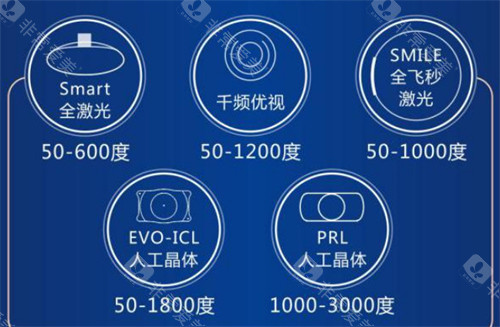

晶体选择是费用差异的核心来源,政策免费提供的为国产基础型单焦点晶体,满足基本视力好转需求。若申请者希望选择功能更优的晶体,需自付差价:

进口单焦点晶体:1400-12000元

高端功能性晶体(如三焦点、景深延长型晶体):15000-30000元起